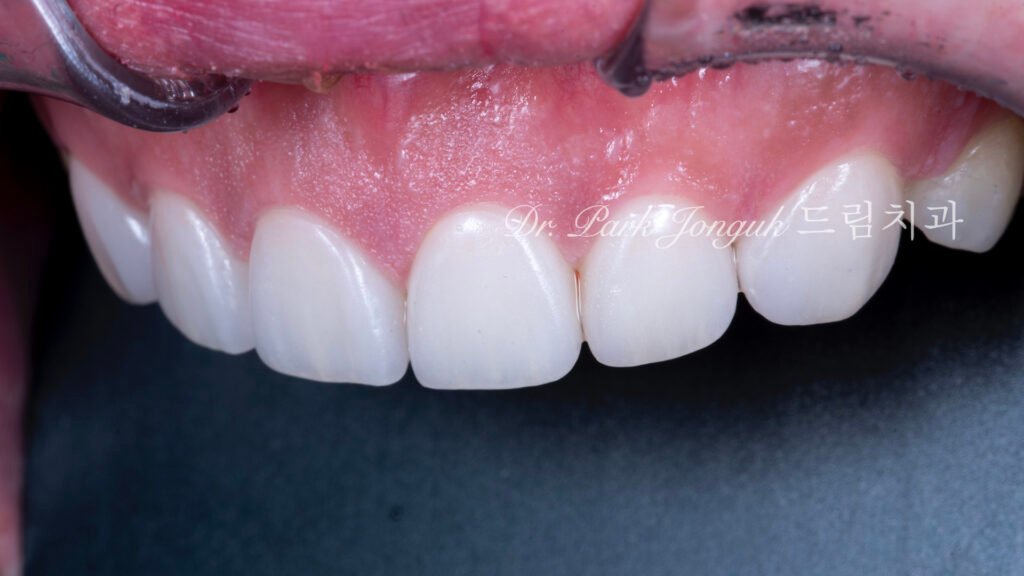

5. 최종 복원: 자연미의 극대화 (사진 6, 7, 8)

5.1 무삭제 라미네이트의 완성

[사진 6, 7, 8 참조] 0%의 삭제율로 완성된 최종 결과물입니다.

- 기능적 보호: 위산에 의해 약해진 치아 표면을 강도 높은 세라믹이 보호막처럼 감싸주어 추가적인 부식을 차단합니다.

- 광학적 재현: 기계로 깎아낸 Monolithic 방식이 아닌, 숙련된 기공사의 **핸드메이드 빌드업(Build-up)**을 통해 자연치 특유의 투명도와 질감을 재현했습니다.

- 심미적 조화: 교정으로 바르게 정렬된 치열 위에 정밀 설계된 라미네이트가 더해져, 부자연스러운 돌출감 없이 조화로운 미소를 완성했습니다.